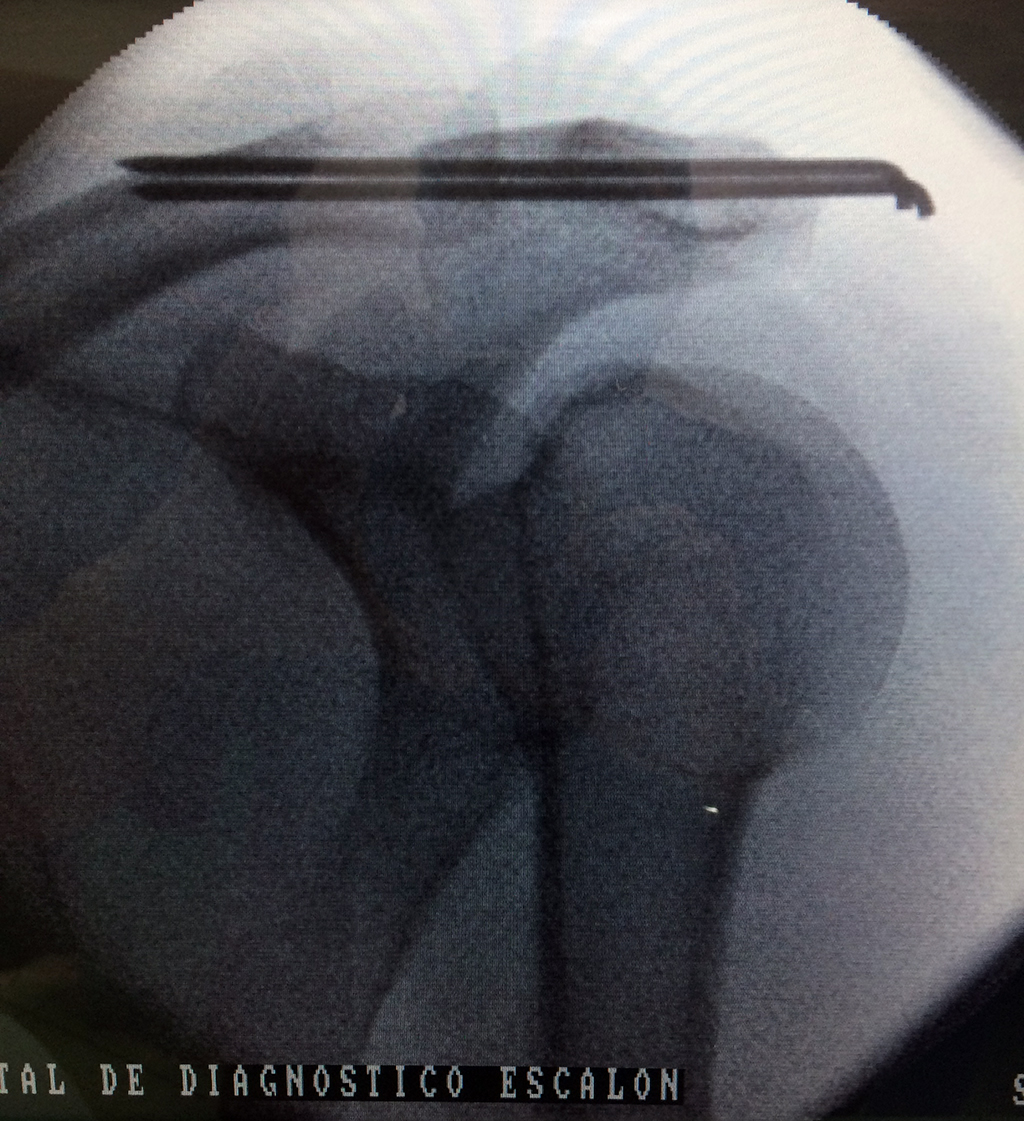

Cirugías de Codos - Clavícula

La clavícula es un hueso largo, con forma de "S" itálica, situado en la parte anterosuperior del tórax. Junto con la escápula forman la cintura escapular. Se puede palpar por toda su longitud y se extiende del esternón al acromion de la escápula, siguiendo una dirección oblicua lateral y posterior.